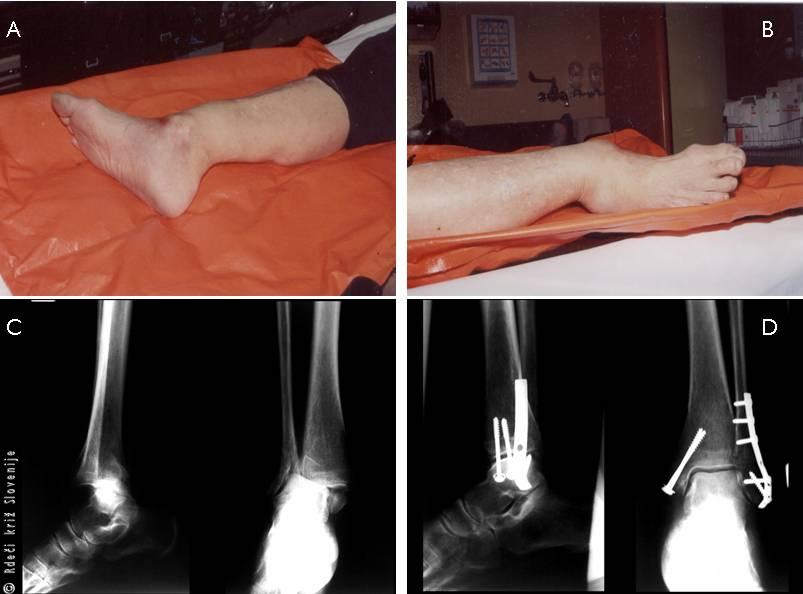

Slika 8

A, B – Izgled zloma gležnja.

C, D – RTG slike zloma gležnja pred in po operaciji.